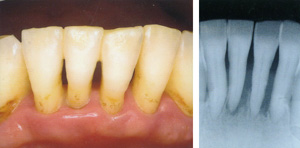

歯周病と骨吸収ーノーブルデンタルクリニック仙台 仙台駅東口 日曜診療 夜間診療